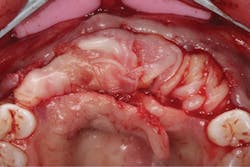

The patient was allowed to heal for three months before returning to uncover the implants. Full thickness flap incisions and retraction of Nos. 5–11 noted bone growth over the implants. We placed polyetheretherketone (PEEK) abutments over the implants to fabricate a fixed screw-retained provisional chairside (figure 9). We grafted once again with PRF, mineralized freeze-dried bone allograft, and fusion bone binder to thicken the area. One horizontal suture was placed from Nos. 7–10. One vertical mattress suture was placed around the No. 5 implant to obtain secondary healing, tucking the PRF membranes over the bone graft on the buccal and lingual tissue and keeping them exposed on the occlusal surface where the temps were screwed in (figure 10) . We allowed this to heal for two months before bringing the patient back to start the restorative phase of treatment (figure 11). During this time, the tissue was able to thicken with the added PRF and additional bone graft added around the implants.

Figure 9: PEEK abutments screwed into implants to convert to fixed temporaries

Figure 10: Temporaries screwed into PRF